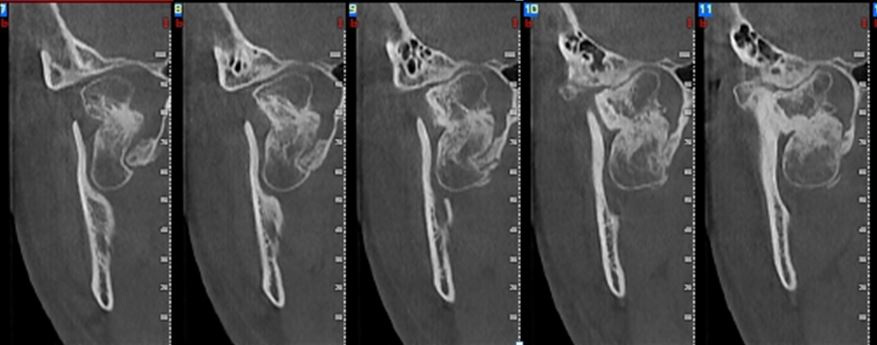

Osteochondroma .

- Imaging features: irregularly shaped radiopaque mass attached to the condyle causing enlargement of the condylar head.